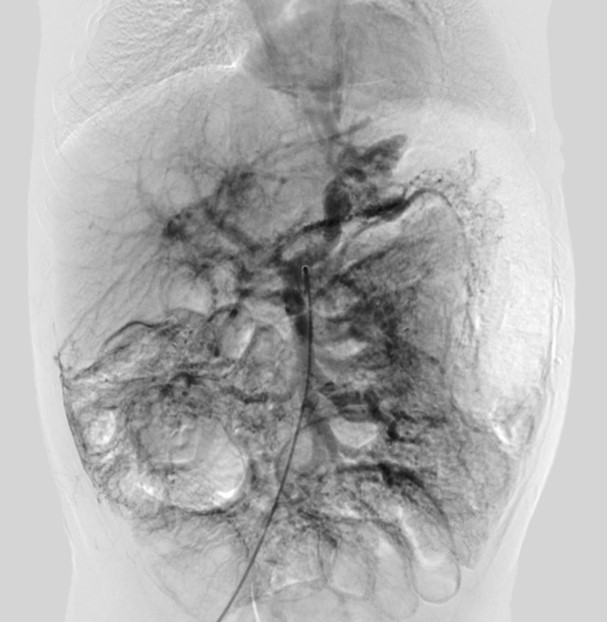

После обследования ребёнку проведено мезентерико- портальное шунтирование (рис. 2). В качестве доступа была выбрана верхняя срединная лапаротомия. Далее по ходу круглой связки печени была выделена и вскрыта левая ветвь воротной вены, выделены верхняя брыжеечная и селезёночная вены. В качестве шунта была использована левая внутренняя ярёмная вена. Диаметр анастомозов между шунтом, верхней брыжеечной и левой воротной веной составлял 7–8 мм. После интраоперационной проверки кровотока раны были ушиты наглухо. В послеоперационном периоде на протяжении 3 мес. ребёнок получал антиагрегантную терапию (аспирин в дозе 15 мг в сут) и ингибиторы протонной помпы в стандартной возрастной дозировке.

Рис. 2. Интраоперационная картина

Fig. 2. Intraoperative picture.